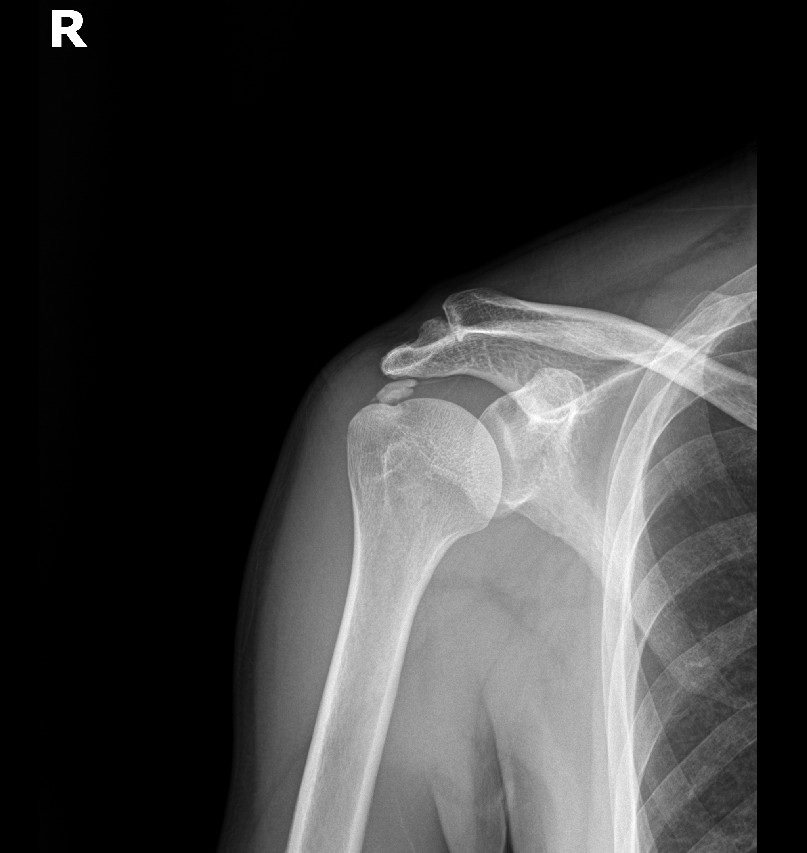

Step 6: 최종 확인 및 마무리

초음파와 X-ray로 석회 제거 확인 후 마무리합니다.

초음파: 석회 부위 확인

X-ray: 석회 완전 제거 확인

X-ray: 약 1.3cm 석회 (휴지기)

시술 직후 X-ray에서 석회 완전 제거 확인